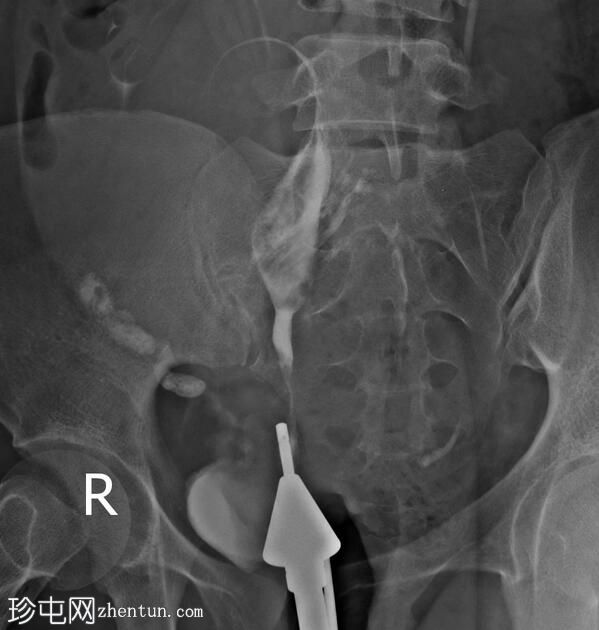

手术开始三分钟后,造影剂进入肾脏,充盈肾盂肾盏系统,然后流入输尿管和膀胱,形成类似于静脉肾盂造影(IVP)的影像

子宫输卵管造影术中出现类似静脉肾盂造影的影像提示可能存在输卵管阻塞,这是由于造影剂流入输卵管并随后流入性腺静脉受阻所致。